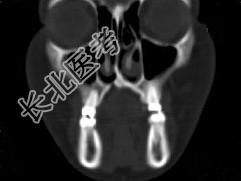

- 单项选择题男,14岁, 脓涕,头痛, CT检查如图,最可能的诊断是 ( )

A、右上颌窦炎

B、腭裂,右上颌窦炎

C、颅面骨发育不良

D、上颌骨骨结核合并瘘道形成

E、上颌骨骨脓肿并瘘道形成